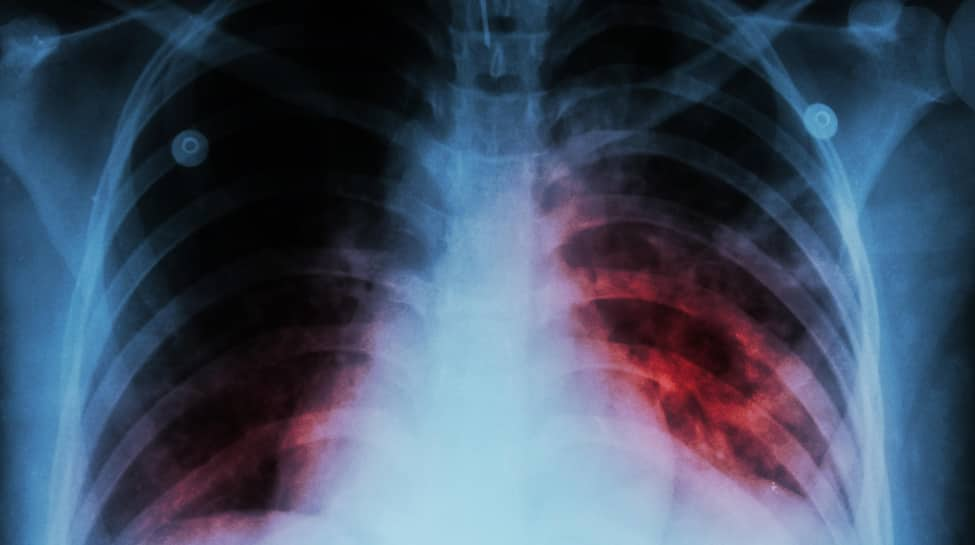

New Delhi: The Centre on Tuesday stated that about 21.69 lakh tuberculosis (TB) cases have been notified between January and October 2024.

“Notified TB cases increased from 18.05 lakh in 2020 to 25.52 lakh in 2023,” said Union Minister of State for Health and Family Welfare, Anupriya Patel, in a written reply in the Rajya Sabha.

“About 21.69 lakh TB cases have been notified between January and October in 2024,” she added.

“The incidence rate of TB in India has shown a 17.7 per cent decline from 237 per 100,000 population in 2015 to 195 per 100,000 population in 2023. TB deaths have reduced by 21.4 per cent from 28 per lakh population in 2015 to 22 per lakh population in 2023,” Patel said.